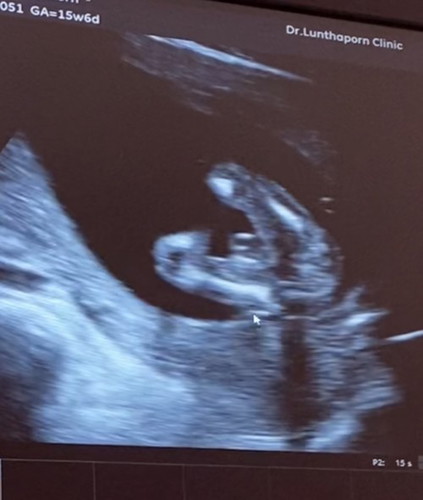

รบกวนแม่ๆช่วยดูเพศหน่อยค่ะ🥰

รบกวนแม่ๆที่มีประสบณ์การ ช่วยดูหน่อยค่ะว่า ผู้หญิงหรือผู้ชาย คุณหมอคล้ายๆจะผู้หญิง แต่ไม่ชัวร์ค่ะ ^^

น่าจะหญิงนะคะ ไอ้ที่ยื่น ๆ มารก ภาพแรกเหมือนไข่ แต่ภาพที่ 2 ชัดเลย